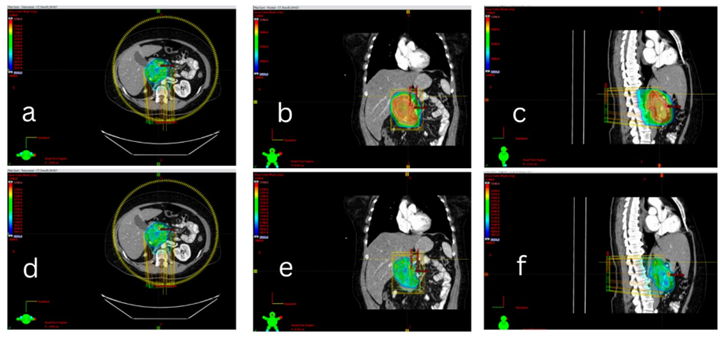

The case was reviewed at the tumor board, and the consensus was to defer stem cell transplantation and proceed with definitive radiation treatment. The patient therefore received a total of 50Gy in 25 fractions (36Gy in 18fractions for the initial phase followed by a 14Gy cone down) between 04/28/21 and 06/02/21, in accordance with the recommendation of The International Lymphoma Radiation Oncology Group (ILROG) for the use of Radiation Therapy (RT) in hematological diseases [12] (figure 2). The patient was treated with deep inspiration breath hold (DIBH). Image-guidance was used with daily KVs, CBCTs and intrafractional monitoring. The patient was NPO 3 hours prior to her daily treatments.

Figure 2: (a), (b) and (c)- 36 Gy coverage and (d), (e) and (f)- 50 Gy coverage; Images from our institutional radiology department.